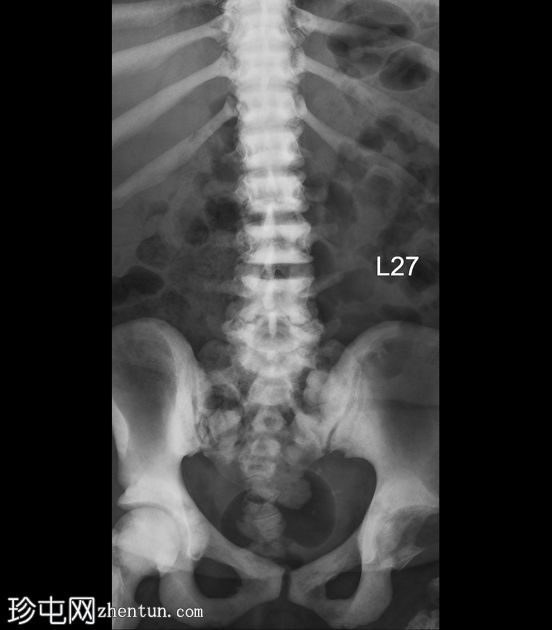

X线片

正位

侧位

弥漫性骨硬化,符合骨硬化症病史。无急性骨折。左髋关节慢性脱位。